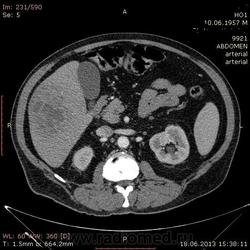

- https://radiomed.ru/sites/default/files/styles/case_slider_image/public/user/17529/img-0004-00001_3.jpg?itok=X4UUizDT

На абсцесс похоже

+1. Контраст вводили?

На мой взгляд, абсцесс.

Тоже за абсцесс.

Cпасибо , коллеги.Сегодня больного прооперировали диагноз абсцесс правой доли печени.Оказывается больной когда - то получил тупую травму живота, об этом нам не говорил.....